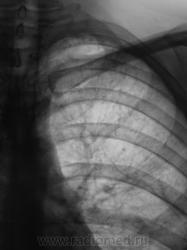

Очаговый ТБС л-х, ф инфильтрации. Осложнение - 2стор. экссудативный плеврит.

Паракостальный двусторонний плеврит,срава - от ключицы до купола(осумкованный),слева-от 5 до 8 ребра.Викарная эмфизема слева.

Сливная долевая пневмония в средней доле справа, очаги справа в верхней доле, экссудативный, частично осумкованный задний правосторонний плеврит. Обязателен анализ экссудата после пуннкции и контрольные снимки, чтобы не пропустить тбс, но он маловероятен - быстрая? динамика

Осумкованные плевриты, оч.твс левого л-го ст. кальцинации.

Осумкованный выпот в плевральных полостях с 2-х сторон, справа по задней пристеночной плевре.На прямой томограмме на 8см. очаговоподобные тени( туб. очаги?).Можно предположить, осумкованный плеврит спицефической этиологии.

Правосторонний паракостальный осумкованный плеврит, в Д-2 полиморфные очаги. Слева плевр. наслоения, небольшое паракост. осумкование, в верхушечном сегменте (1-2) очаги, лимфангит, уплотнение апикокост. плевры.

Да, у пациента диагностирован и подтверждён двусторонний очаговый туберкулёз и задний паракостальный осумкованный плеврит.